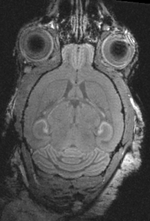

shown are, from left to right, panels of axial, sagittal and coronal views.

original brain in proper RAS orientation original,after reorientation into RAS

original unregistered brains original, not registered